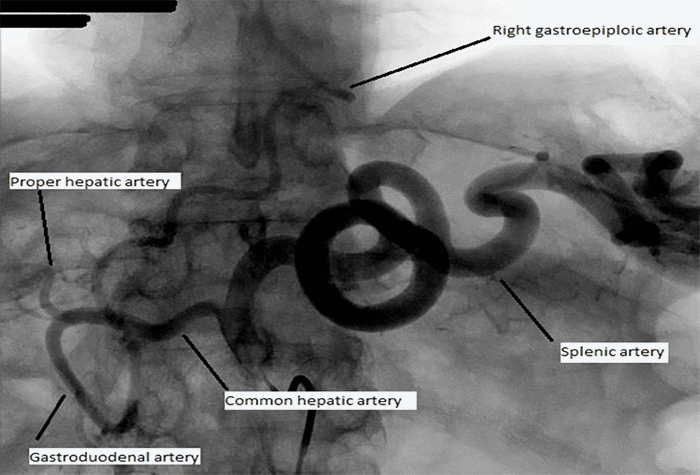

Following a clinic discussion, the patient opted for surgical resection of the ampullary lesion. Preoperative angiography (Figure 2) delineated the gastric conduit’s vasculature, confirming exclusive reliance on the right gastroepiploic artery and demonstrating no contributions from the SMA or short gastric arteries, as suggested by prior axial imaging (Figure 3). The patient completed a bowel prep the evening before surgery, allowing for the possibility of colonic interposition.

Figure 2. Preoperative Diagnostic Angiogram of Gastric Conduit. Published with Permission

Right gastroepiploic artery is the primary supply to the conduit following prior esophagectomy. Left gastric and short gastric arteries have been ligated. Right gastric artery, though likely patent, is diminutive